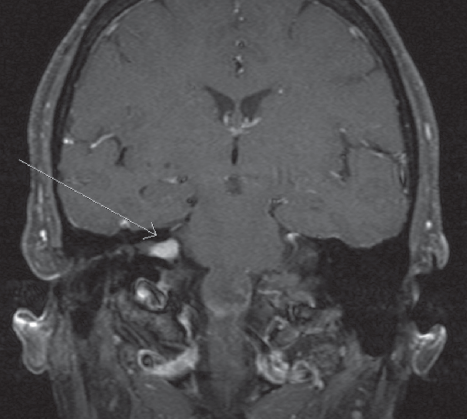

Navid Farajipour, MD; Rex D. Wilford, DO, RPh

A 57-year-old female with a past medical history of diabetes mellitus type 2 presented with a chief complaint of dizziness, nausea, and vomiting.